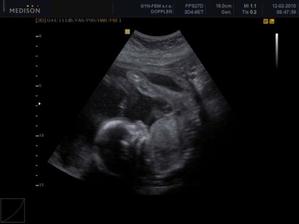

30.12. Jsem se byla zaregistrovat k porodu u Apolináře. ROK 2010 🙂 TO SE BUDOU DÍT VĚCI. 12.1. interní vyšetření + EKG a odběr - všechno OK, 14.1. UTZ žil kvůli natékání nohou (už ráno mám kotníky jako bambule). Výsledek: tromboza nehrozí UF!, nedomýkavost chlopní tepen, pže tělo je víc zatíženo. Doporučeno: nosit těhu punčochy, hodně pít, víc chodit, málo sedět a stát. Pak jsem utíkala na gyn na triplle testy a sestra mě objednala i na velký UTZ kam půjde i manža a budeme mimíska mít na DVD. Jsme oba natěšený! 20.1. UTZ ledvin - vše v pořádku. Tak velký UTZ proběhl OK. Nechceme vědět co to bude tak to stále nevíme 🙂)) . Triplletesty jsou taky v pořádku. 18.2. poradna - tak jsem měla nízký tlak 🙂)) jindy ho mám vysoký tak jsou trošku zmatený. Říkám, že mají blbý tlakoměr. Gynekologicky a miminkovsky všechno dobrý. 21.2. domluveno jméno pro klučíka - TOMÁŠEK .... ještě tu holčičku 😉)).